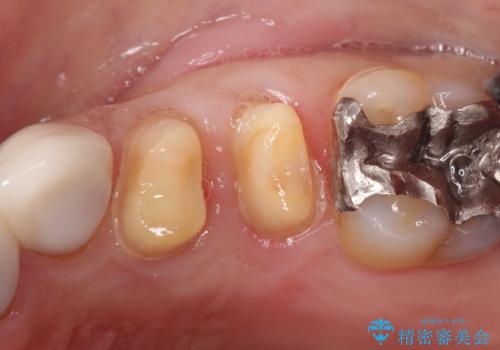

縁下カリエス オールセラミッククラウン

- 以前他院で修復した金属の詰め物の下が虫歯になっており、歯周外科を含めた歯冠修復を行っております。

- 27万円費用は治療当時の料金となります